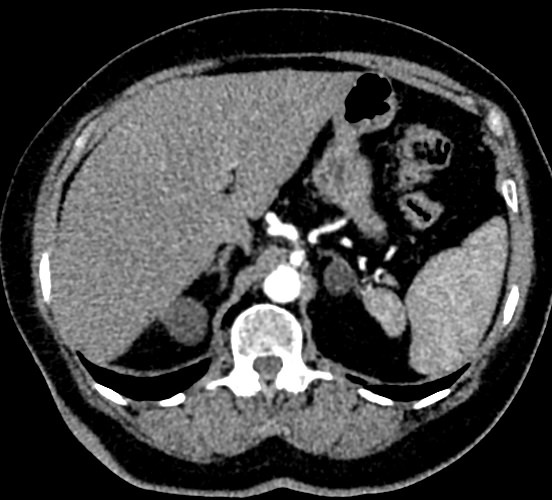

Мультиспиральная компьютерная томография селезенки – высокоинформативный лучевой метод исследования, основанный на использовании рентгеновского излучения и позволяющий детально визуализировать паренхиму селезенки, состояние близлежащих органов и тканей, питающих ее кровеносных сосудов и регионарных лимфоузлов.

МСКТ селезенки проводится как с использованием контраста, так и без него. Контрастирование применяется для выявления патологических очагов, которые могут быть не видны при нативном исследовании. Для этого внутривенно вводится контрастный препарат, содержащий йод и накапливающийся в патологических очагах опухолевой и воспалительной природы.

Мультиспиральная компьютерная томография селезенки с внутривенным болюсным контрастированием используется в диагностике гематологических заболеваний, опухолевых процессов, при планировании хирургического вмешательства и для отслеживания эффективности лекарственной терапии.